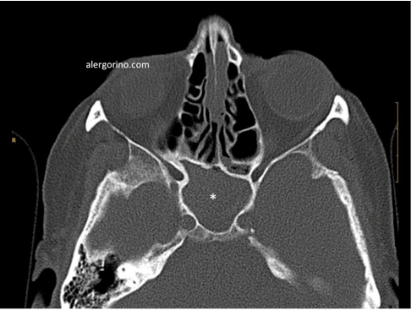

El diagnóstico se realiza mediante la historia clínica y una endoscopia nasal que proporcionan datos como la presencia de pólipos, la descarga mucopurulenta y el edema o la obstrucción de las áreas de drenaje de los senos paranasales. Si no se produjera una respuesta al tratamiento médico se evalua la situación de los senos paranasales mediante una tomografía computarizada (TC).

Los objetivos del tratamiento son: controlar la infección, reducir el edema del tejido, facilitar el drenaje, mantener la aireación de los senos paranasales, rompiendo el ciclo vicioso que conduce a la cronicidad. El tratamiento de la SC, con y sin póliposis, suele puede ser "en bocadillo": médico – quirúrgico – médico. Principalmente los lavados nasales en forma de duchas nasales, corticoides intranasales, antibióticos en caso de sobre-infección. La cirugía endoscópica está indicada cuando fracasa el tratamiento médico. En caso de la SC fúngica es imprescindible la apertura y limpieza adecuadas de los senos afectados.